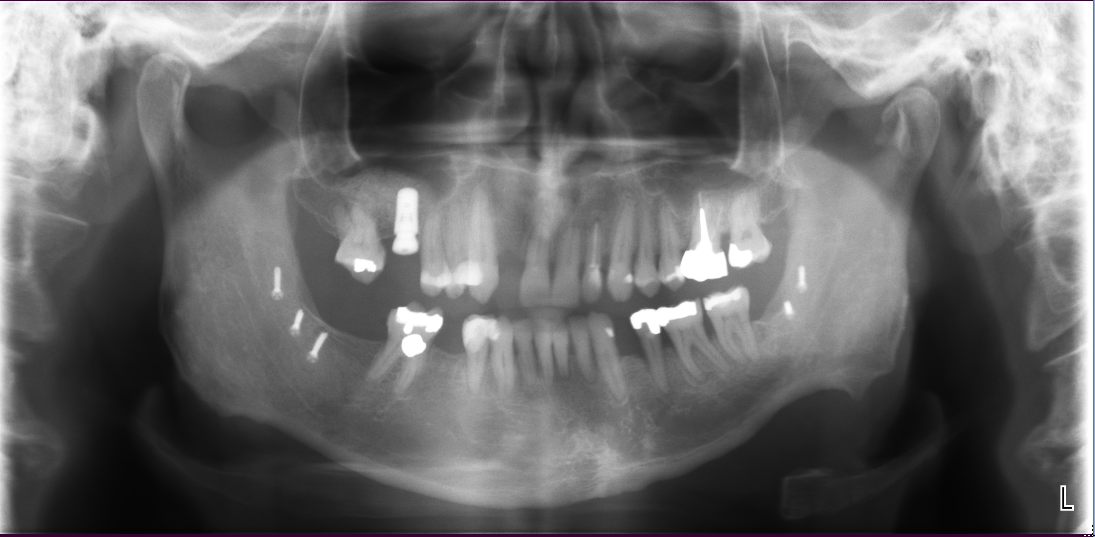

Sinus Lift Implant Vancouver Burnaby Periodontist Implant Dentist IMPreESS Perio

Dental Implant Centre in Vancouver Burnaby Sinus Lift Dental implant Surgery Dr. Noroozi Implant Specialist IMPrESS Perio Implant Center.001

Sinus Lift, Bone Graft, Implants Dr. Noroozi IMPrESS Perio Implant Center

The bone used in a sinus lift may come from your own body (autogenous bone), from a cadaver (allogeneic bone) or from cow bone (xenograft). You will need X-rays taken before your sinus lift so the dentist can study the anatomy of your jaw and sinus. You also may need a special type of computed tomography (CBCT) scan. This scan will allow the dentist to accurately measure the height and width of your existing bone and to evaluate the health of your sinus.